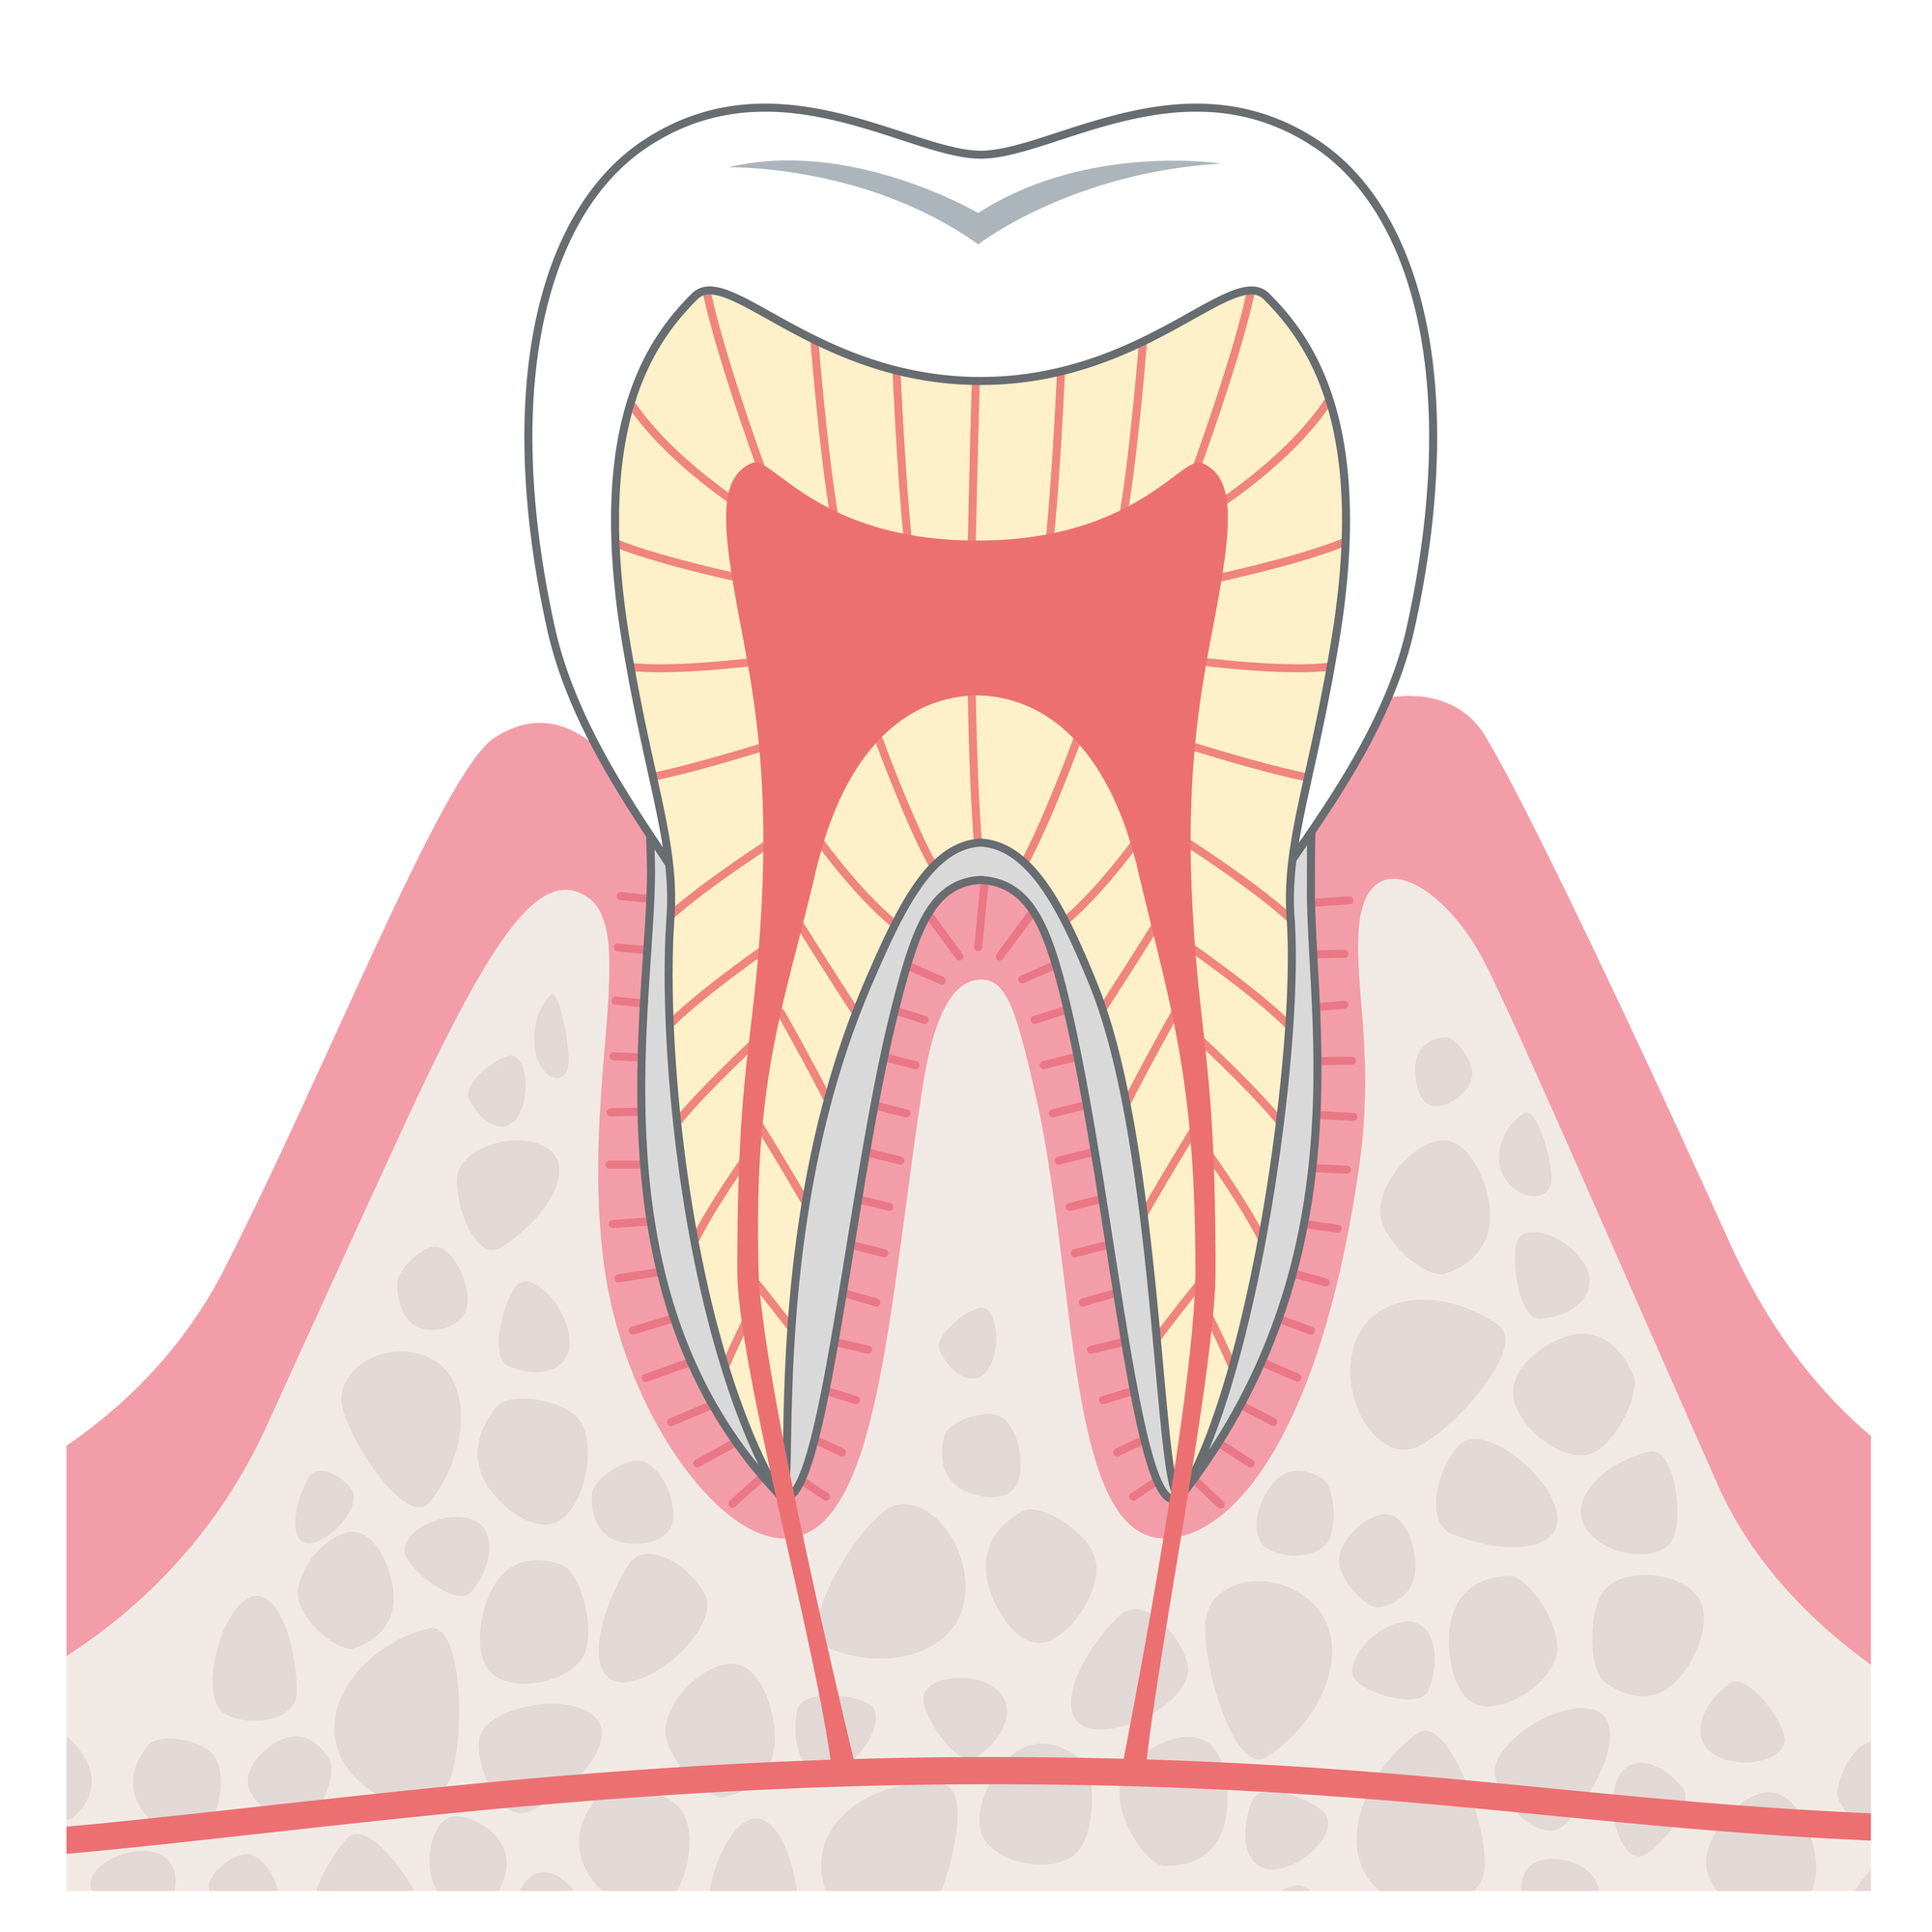

むし歯の進行と治療内容

C0

COの段階は、むし歯が始まった初期段階です。歯の表面が溶けていきます。

痛みなどの自覚症状がなく、むし歯に気付かないことが多いです。

C1

C1の段階では、むし歯菌がエナメル質を溶かします。痛みはありません。

この段階で治療をできると理想的です。

C2

この段階のむし歯は自然に治ることはないため、放置せずお早めの受診がおすすめです。

C3

C3は、むし歯が神経にまで達しています。痛みが強くなり、膿が出たり、腫れたりします。

C4